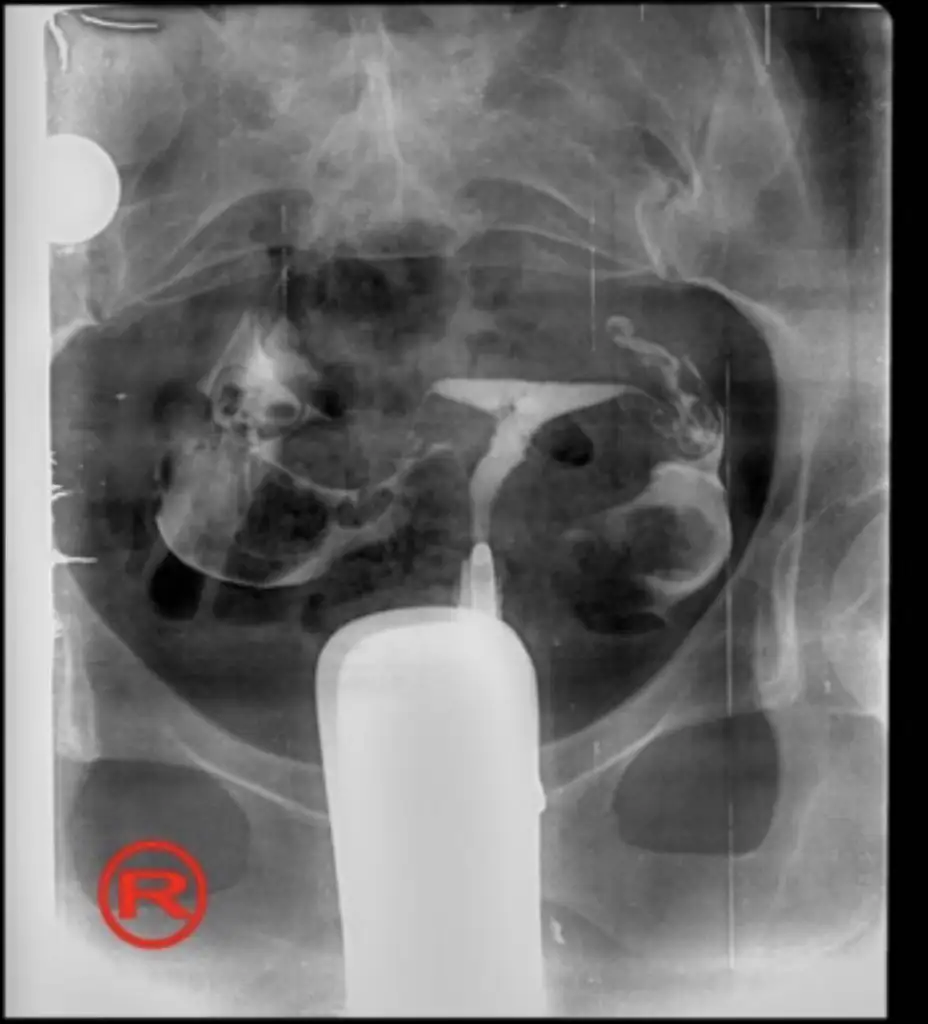

Canım sana atıyorum rahmimi şimdi doktor bana bu t rahim hafif düzeyde dedi 6-8 haftada ölüyor bebeklerin bu ona sebep olmaz dedi ama hepsi öldü 11 ay içinde 3 bebek kaybetmek ne demek doktorlar bilmez çünkü Allah bir daha yaşatmasın çok geçmiş olsun sana da inşallah düzelince yeniden hamile kalıp kucağıma alabilirim 💚 Rabbim sana da hayırlı evlatlar nasip etsin inşallah. aşağıya ekledim bu rahme çok az t dedi ameliyata gerek yok dedi

• 03792326-2AFC-4D55-85B7-6F27258A58EB.webp

03792326-2AFC-4D55-85B7-6F27258A58EB.webp

20,1 KB · Görüntüleme: 50